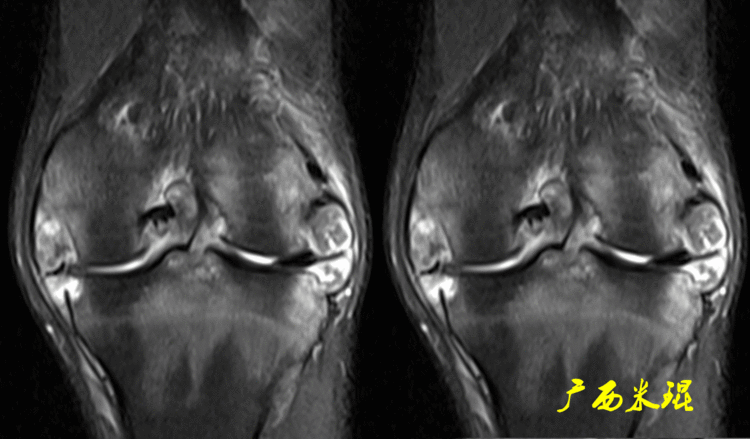

下面这张MR冠状位显示为内侧半月板后角的假桶柄,其母体(图片中内侧的那一部分半月板)并没有变小、形态及信号均正常。

下面这张MR冠状位显示为外侧半月板后角的假桶柄,尽管在髁间窝发现半月板信号,但其母体(图片中外侧的那一部分半月板)并没有变小、形态及信号均正常。